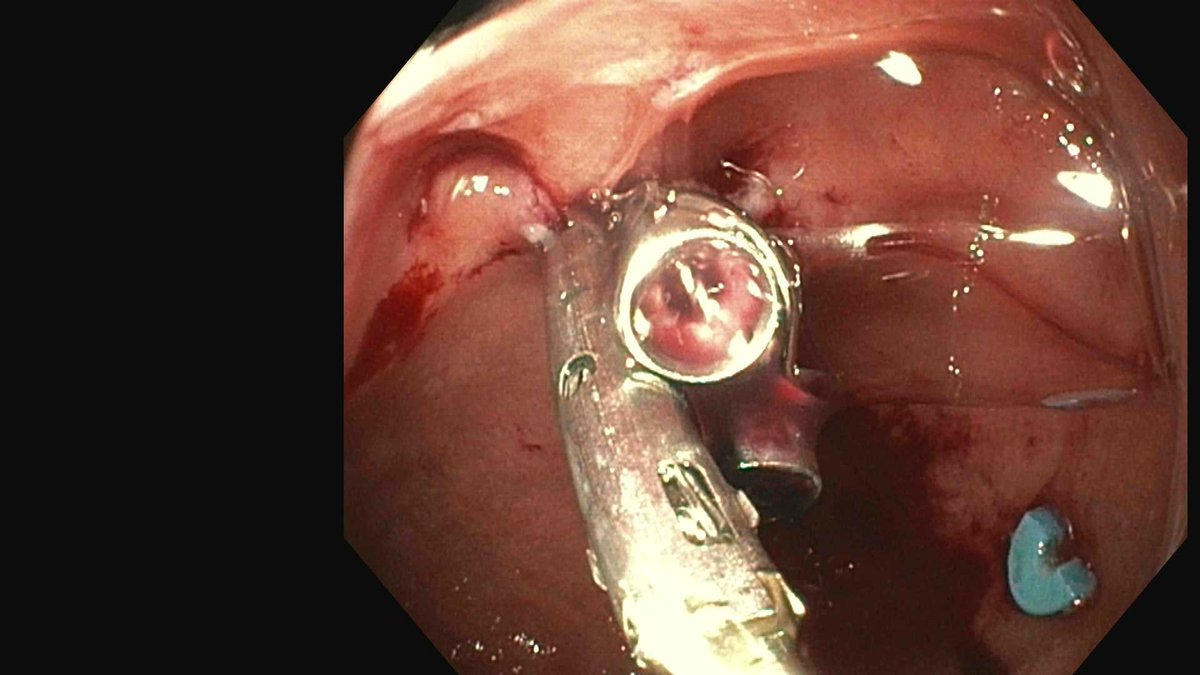

Primer contacto con sutura endoscópica X-Tack Boston Scientific Cierre de escara pólipo LST NG IIA-IIC ángulo hepático de 25 mm. Buenas sensaciones. Ahí va video: TOMAS FUSTER BELLIDO DS Gandia Suan Machado Vanessa Carlos Boix Clara Navarro Mariló Carolina Mangas-Sanjuan @olcina_p

Colocación de HotAxios en DS Gandia Colecistogastrostomia en ADC páncreas pendiente inicio neoadyuvancia con shock séptico por obstrucción del cístico. Vanessa Carlos Boix Clara Navarro Pablo Olcina Gloria Alemany Perez Mariló TOMAS FUSTER BELLIDO Gracias Belen Martinez Moreno

Rendez vous asistido por Rx intervencionista con técnica en monorail de José Ramón Aparicio usando un esfinterotomo de Boston Scientific Endoscopy modificado tras dos cpre fallidas e imposibilidad de drenaje percutaneo interno-externo . Pablo Olcina Vanesa M. Escapa Salvador Benlloch DS Arnau-Lliria

Endoscopic mucosal resection (EMR) of a neuroendocrine tumor in the duodenal bulb. We used the Boston Scientific Endoscopy Captivator kit to good effect. #gitwitter #surgery #oncology